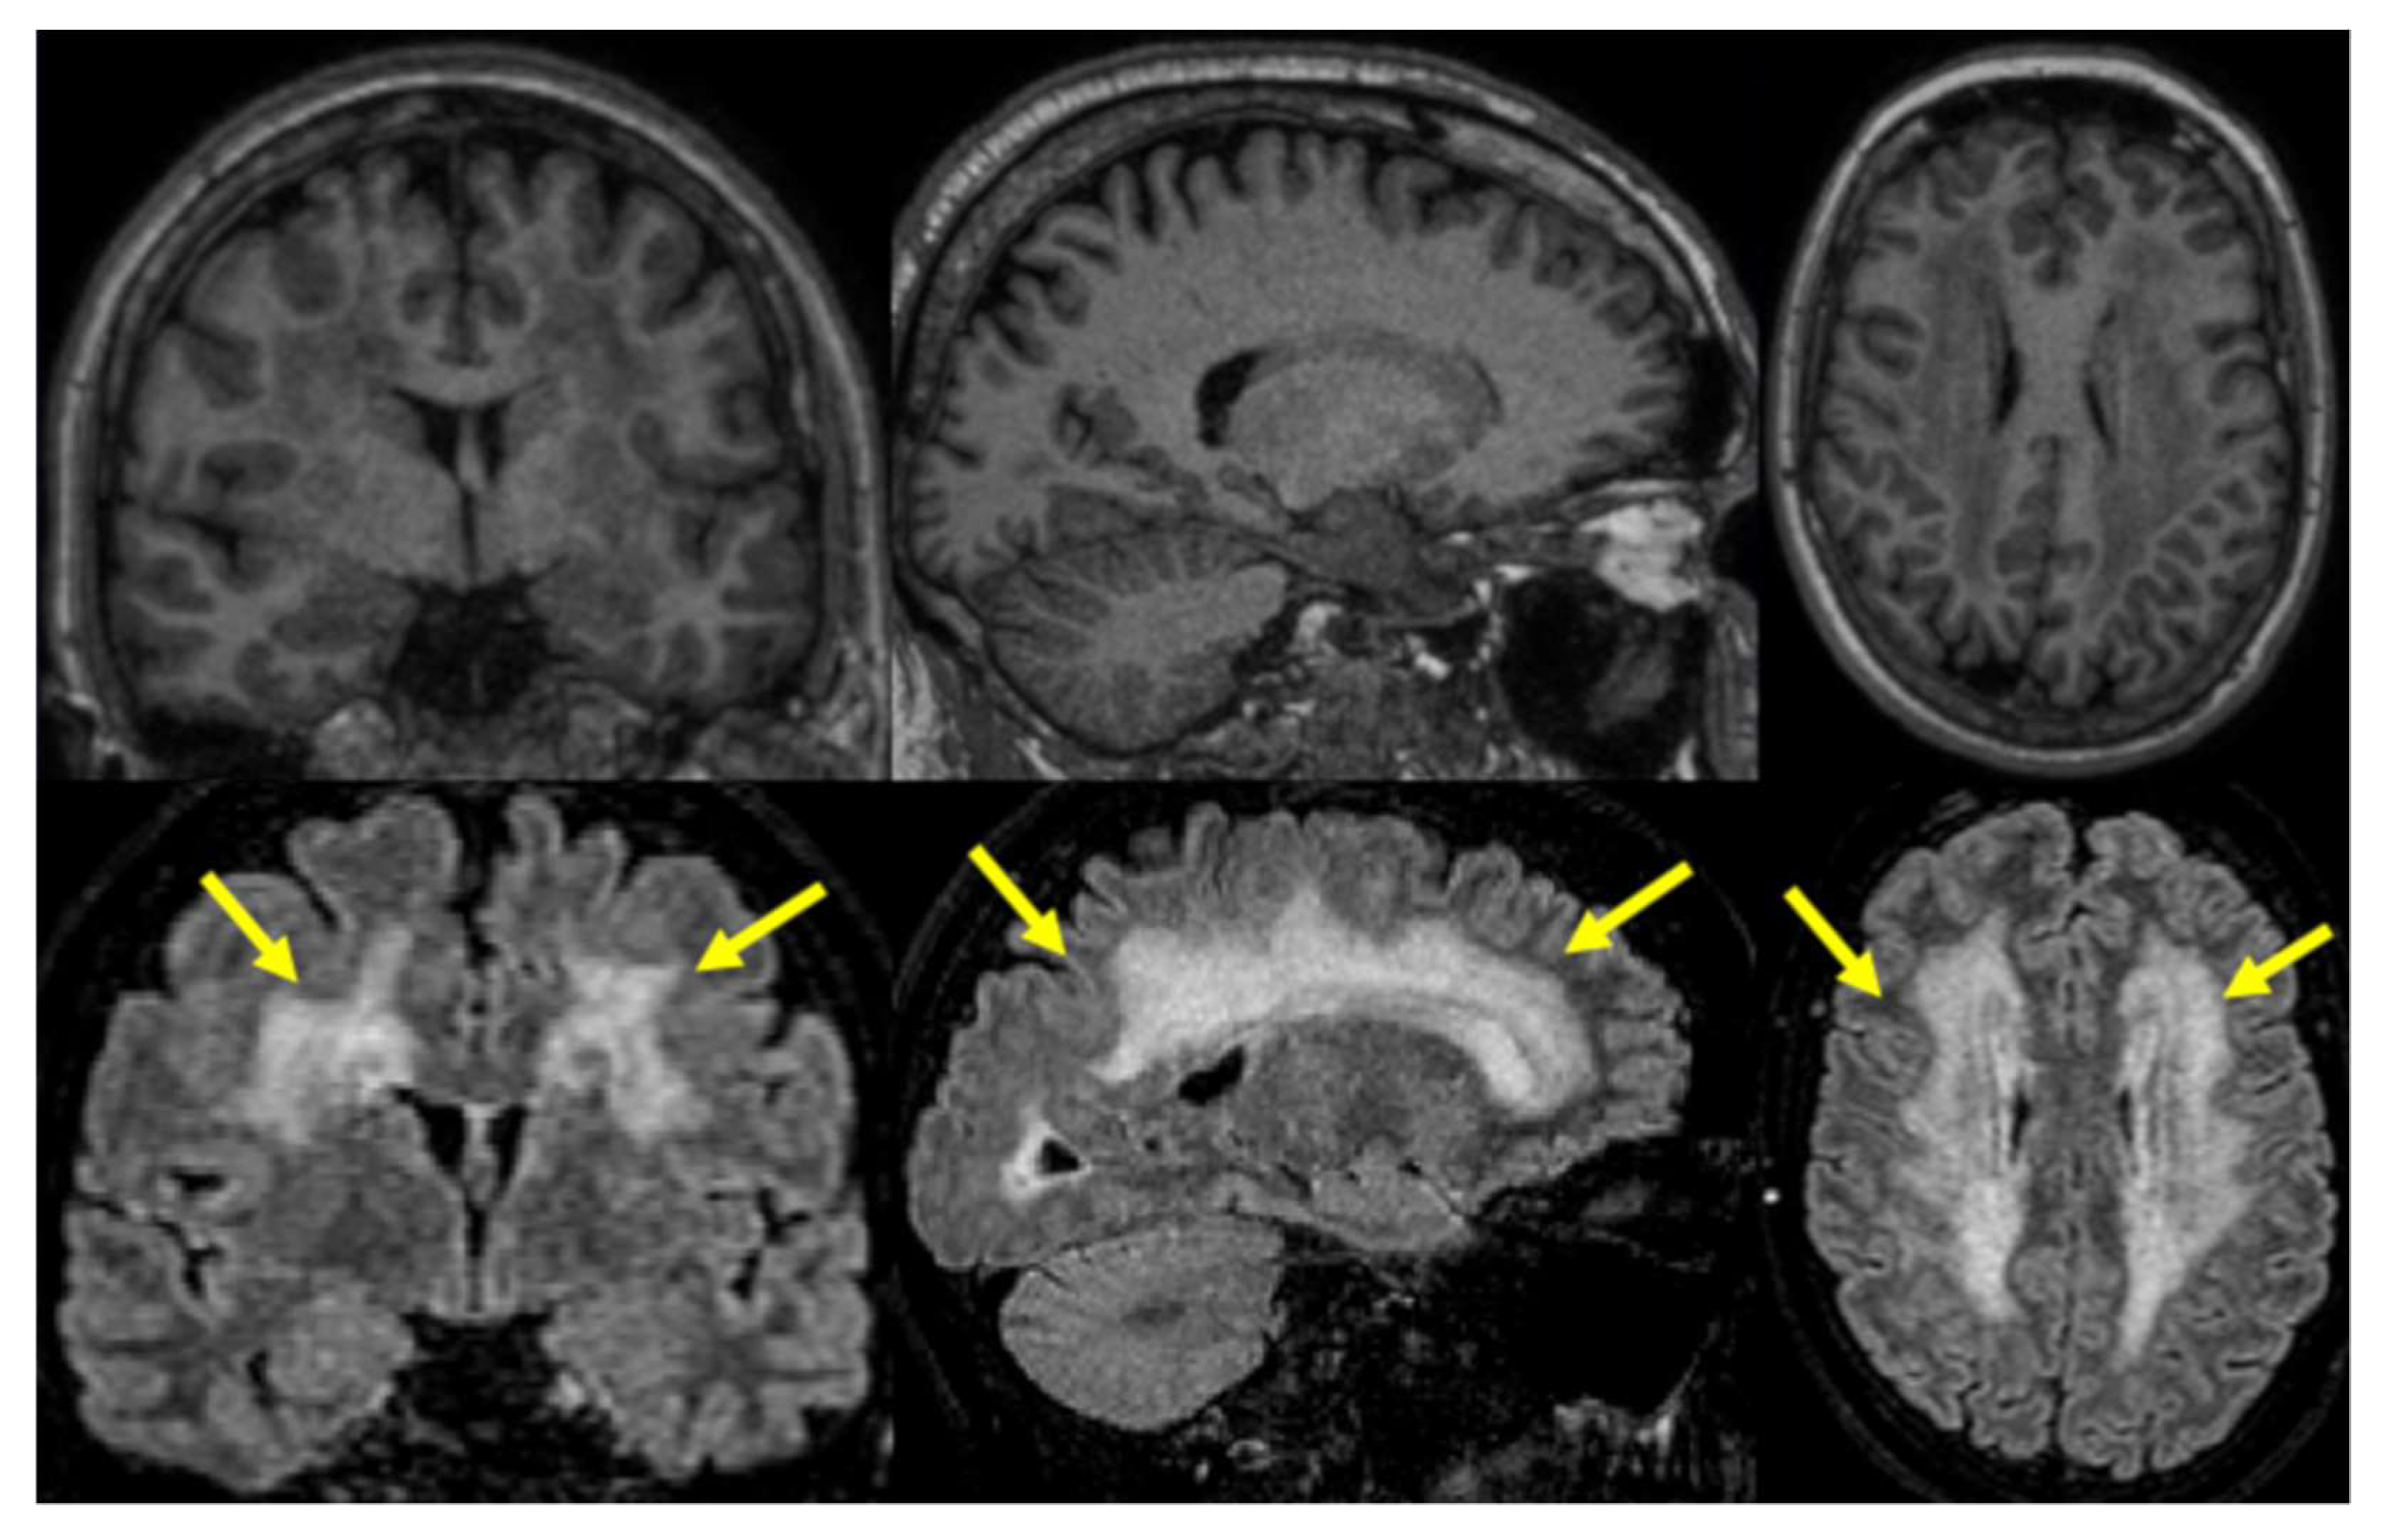

3.4. MRI Findings

| Fazekas Score | Skogholt Group n = 11 | MRI Control Group n = 60 |

|---|---|---|

| 0 | 2 (18%) | 13 (23%) |

| 1 | 1 (9.1%) | 36 (64%) |

| 2 | 2 (18%) | 7 (12%) |

| 3 | 6 (55%) | 0 (0%) |

| missing | 0 | 4 |